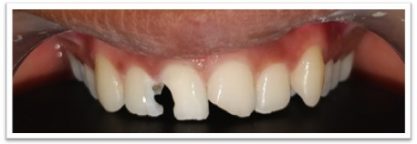

Patient Name:Anil Jagtap

Tooth Involved : 22

Diagnosis : Ellis Class IV Fracture With 22

Treatment : Root Canal Treatment 22

Restoration: Cast Post And Core With Porcelain Fused To Metal Crown.

Before

After